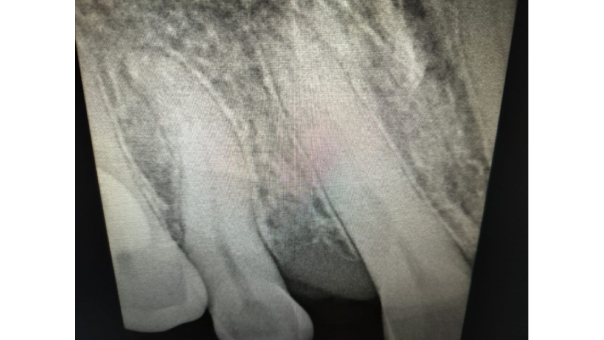

Mesioden In the IOPAR

Diagnosis: Upon clinical and radiographic examination, we discovered the presence of a mesioden—an extra tooth located between her Upper Right Central and Lateral Incisor. This supernumerary tooth was contributing to the spacing and misalignment in the anterior region.

Radiograph after extraction of the mesioden

Radiographs after Rootcanal treatment